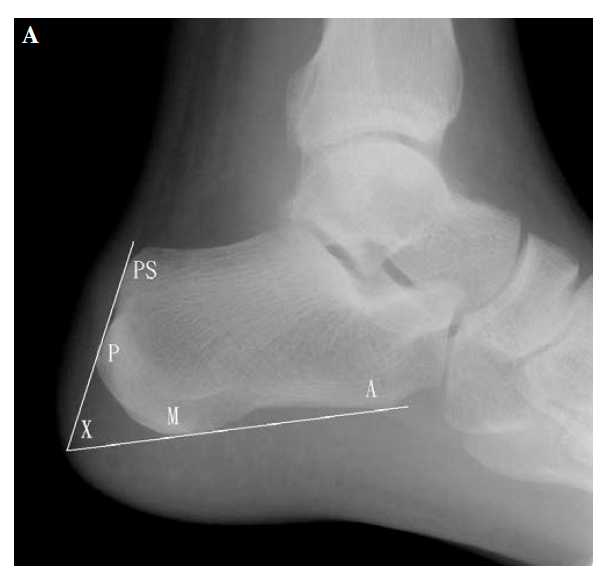

X:Fowler and Philips angle,44°-69°

CLA角:Chauveaux-Liet  Angle,CLA=α-β,>12°怀疑,X/Y值:<2.5高度怀疑

FPA和PPL不可靠,Haglund综合征与跟腱钙化和跟骨后方骨刺关系密切。